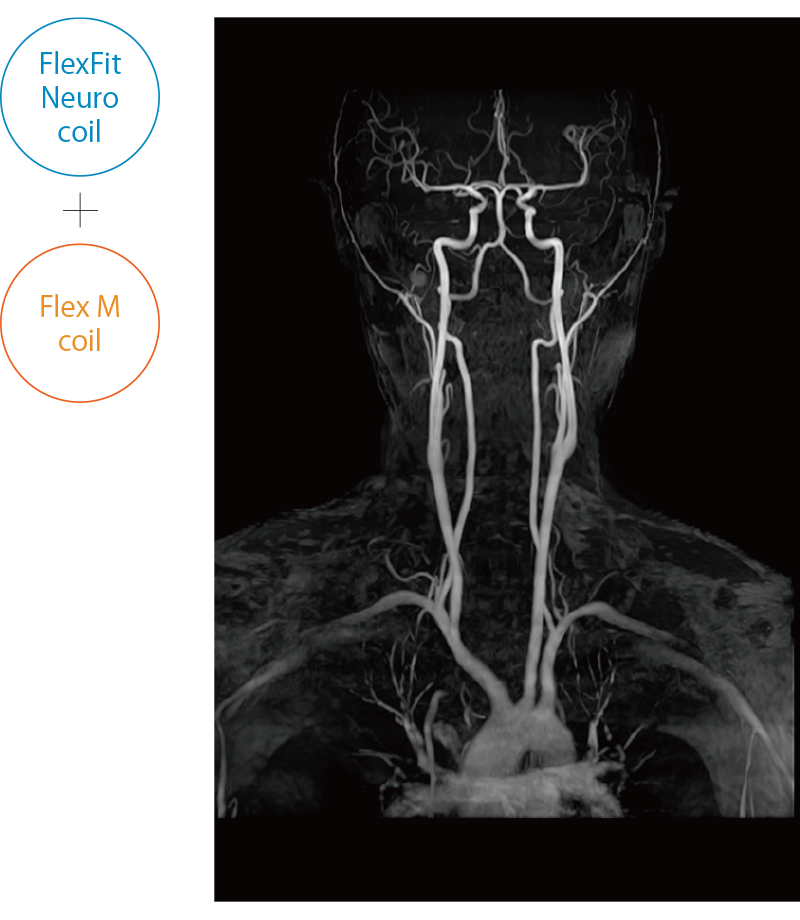

ECHELON Synergy ZeroHeliumはスライド装着でOneアクションセッティング可能なフレキシブル頭頸部用コイルや、撮りたい場所をフレキシブルにワイドにカバーできるFlexコイルを備え、部位に応じて柔軟に対応できます。